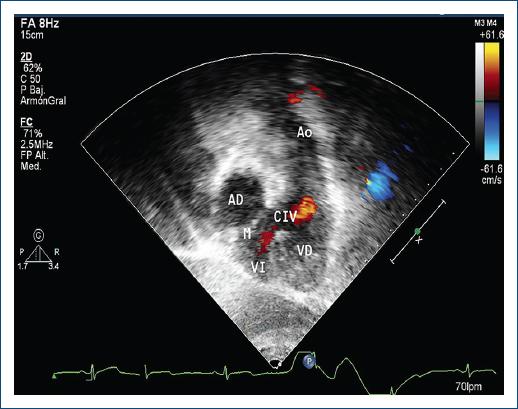

El realizar el diagnóstico prenatal es complicado cuando no se asocia a otras lesiones6. La ecocardiografía transtorácica es capaz de describir con precisión las características de la cardiopatía (Fig. 2) y dar las características preoperatorias y postoperatorias (gravedad de la IT, función del VD, estado actual de la CIV, EP, insuficiencia pulmonar e insuficiencia mitral, evaluación para decisión y seguimiento de doble switch, Rastelli o manejo uni ventricular)5. En una selección de pacientes se pueden incluir otros estudios de imagen como la angiografía, resonancia magnética y tomografía axial5.

Figura 2 Ecocardiograma bidimensional-color en ventana subcostal, donde se observa a la derecha la conexión de la aurícula derecha (AD) con el ventrículo izquierdo (VI) y a la izquierda el ventrículo derecho (VD) conectado a la arteria aorta (Ao) (doble discordancia). Se observa una comunicación interventricular (CIV) como lesión concomitante.